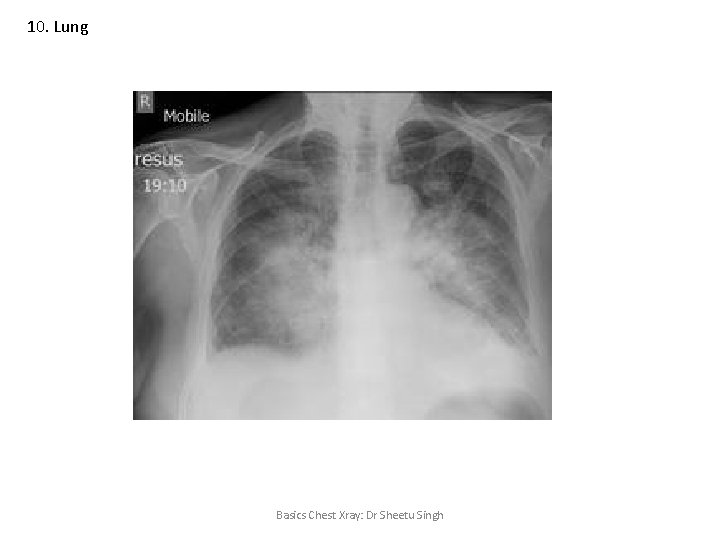

10. Lung Basics Chest Xray: Dr Sheetu Singh

10. Lung Unilateral radiolucency on chest X ray • • • Pneumothorax Emphysema Resection of mammary gland Pulmonary artery obstruction Patient rotation Basics Chest Xray: Dr Sheetu Singh

10. Lung Emphysema • • Flattened diaphragm (terrace pattern) Tubular heart Increased rib spaces Increased retrosternal air spaces Basics Chest Xray: Dr Sheetu Singh